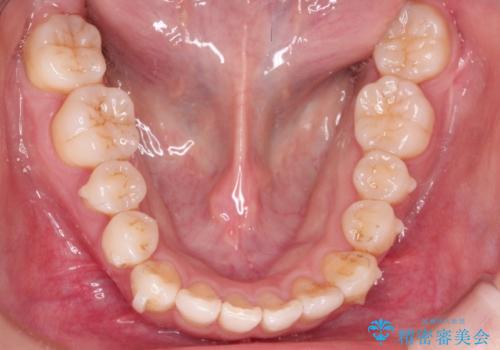

インビザラインで八重歯の矯正

- 八重歯を治したいとのことで、来院されました。

インビザラインにて、上顎の歯と歯の間をわずかに削り、並べる計画としました。